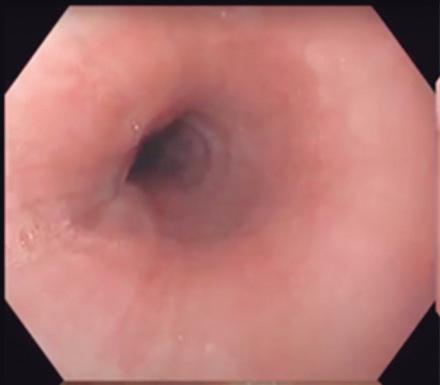

Redefiniendo la evaluación endoscópica

inicial

de los síntomas esofágicos: hacia un paradigma diagnóstico basado en la precisión

Redefiniendo la evaluación endoscópica inicial de los síntomas esofágicos

Introducción

Los síntomas esofágicos, como pirosis, disfagia, regurgitación, dolor torácico e impactación alimentaria, representan una proporción sustancial de las consultas ambulatorias en gastroenterología. Si bien se trata de manifestaciones clínicas frecuentes, las etiologías subyacentes son heterogéneas y, en muchos casos, difíciles de diferenciar basándose únicamente en la historia clínica. La enfermedad por reflujo gastroesofágico (ERGE), la esofagitis eosinofílica (EoE), los trastornos motores esofágicos y los trastornos funcionales del esófago suelen presentarse con perfiles sintomáticos superpuestos. Esto conduce a la ambigüedad diagnóstica y la incertidumbre terapéutica.1

Históricamente, la evaluación de los síntomas esofágicos se ha apoyado en ensayos terapéuticos empíricos, en particular con inhibidores de la bomba de protones (IBP), seguidos de la realización de una endoscopía digestiva alta y, cuando resulta necesario, pruebas funcionales esofágicas. Si bien este modelo se encuentra firmemente incorporado en la práctica clínica habitual, en la actualidad se reconoce de manera creciente que dicho enfoque puede resultar ineficiente desde el punto de vista diagnóstico y poco efectivo para establecer la etiología subyacente de los síntomas en un número significativo de casos. El tratamiento empírico se asocia a un efecto placebo significativo, retrasos en el diagnóstico definitivo y una prolongación innecesaria del malestar del paciente, especialmente en aquellos con trastornos motores esofágicos o trastornos de la interacción intestino-cerebro.2, 3

La endoscopía continúa siendo la piedra angular en la evaluación esofágica debido a su capacidad para excluir malignidad, identificar la enfermedad mucosa y detectar una obstrucción mecánica. Sin embargo, hasta el 50 - 70% de los pacientes sometidos a una endoscopía digestiva alta por síntomas esofágicos no presentan anormalidades evidentes, lo que deja a los clínicos con escasa claridad diagnóstica y a los pacientes con síntomas persistentes.3 En estos casos son necesarias las pruebas funcionales esofágicas -manometría de alta resolución (MAR), monitoreo ambulatorio del reflujo y esofagograma baritado- para establecer un diagnóstico. Lamentablemente, estos estudios suelen realizarse semanas o meses más tarde, requieren derivación a centros especializados y están limitadas por una tolerancia subóptima y una proporción no despreciable de estudios incompletos.2, 3